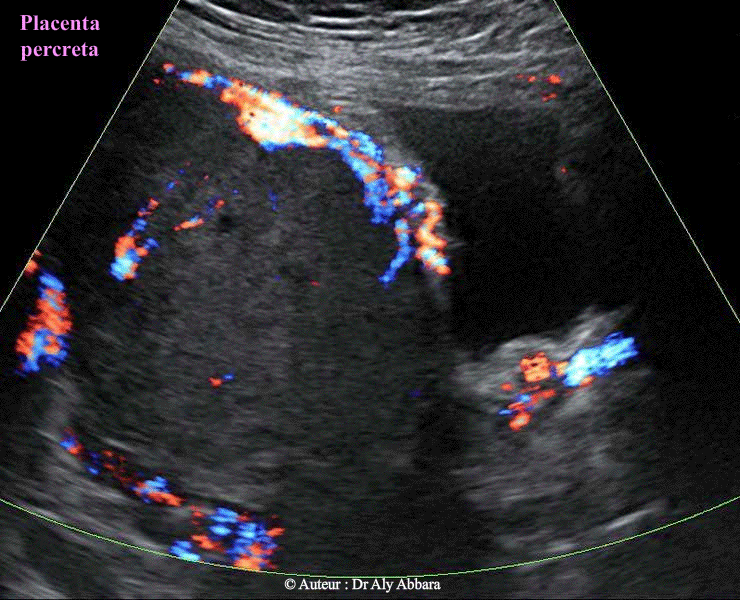

• Images échographiques par voie transpariétale abdominale mettant en évidence certaines caractéristiques échographiques du placenta accreta (type percreta dans cet exemple):

Sur une coupe sagittale (plan vertical, perpendiculaire au plan vu de face maternelle du placenta) on peut distinguer les plans successifs et les signes suivants :

• 1- La paroi abdominale (tissu adipeux sous cutané puis plan musculo-aponévrotique

• 2- La paroi de l'utérus (le myomètre) est absente sur cette coupe

• 3- La caduque basale (ou le liseré hypo ou anéchogène) est également absente

• 4- Le placenta s'insère directement sur la paroi vésicale postérieure

• 5- on distingue grâce au Doppler couleur (Dynamic-Flow) un riche réseau vasculaire dans le plan de l'insertion placentaire ; il s'agit de réseaux veineux, mais sur certaines coupes on trouve des artérioles (spiralés) pénétrant dans la paroi vésicale et visibles dans sa muqueuse

Les images publiées dans cette page ont été réalisées chez une femme enceinte de 28 semaines d'aménorrhée - utérus bi-cicatriciel.

Cliniquement (chirurgicalement) : le diagnostic de placenta percreta est confirmé.